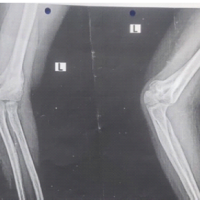

The patient was reviewed regularly in the outpatient department, with close observation of recovery progress. Kirschner wires were removed at 6 weeks post-surgery, and the below-knee immobilization was maintained for a total of 8 weeks. After slab removal, the patient began a supervised physiotherapy program focusing on ankle range of motion exercises, continued over the next 4–6 weeks. Gradual weight-bearing with the assistance of a walking frame was initiated at this stage. By the 4th post-operative month, the patient was ambulating independently without support, and radiographs confirmed satisfactory fracture union (Figure 5,6),. At the 5-month follow-up, ankle mobility had returned to near-normal levels, with both dorsiflexion and plantarflexion ranging from 0 to 15° bilaterally. Further follow-up at 15 months revealed normal range of motions at bilateral ankle (0–15° of plantar and dorsiflexion) with foot and ankle outcome score being 95% (Figure 7-9).